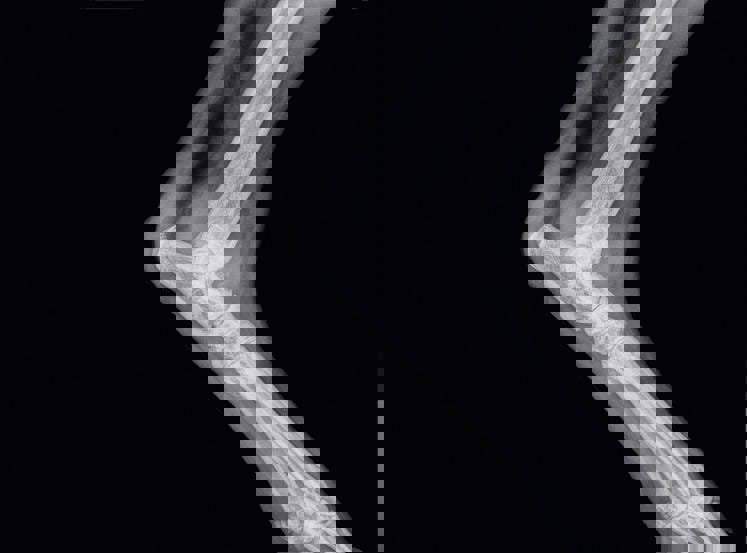

It was discovered that Matt’s previous motorbike accident had damaged the soft tissue in the lower part of Matt’s back. And, whilst he’d been given treatment, the injury left him vulnerable to future back injuries and pain. So, when he’d twisted his body to stop himself from falling, he’d aggravated the same back injury, making it considerably worse.

The nerves at the bottom of his spine were also trapped which was giving him numbness and weakness in his right leg.